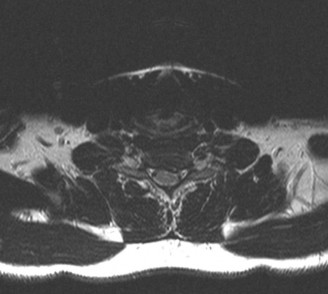

A 63-year-old male sustained a hyperextension injury to his neck while diving into a pool. Upon presentation,…